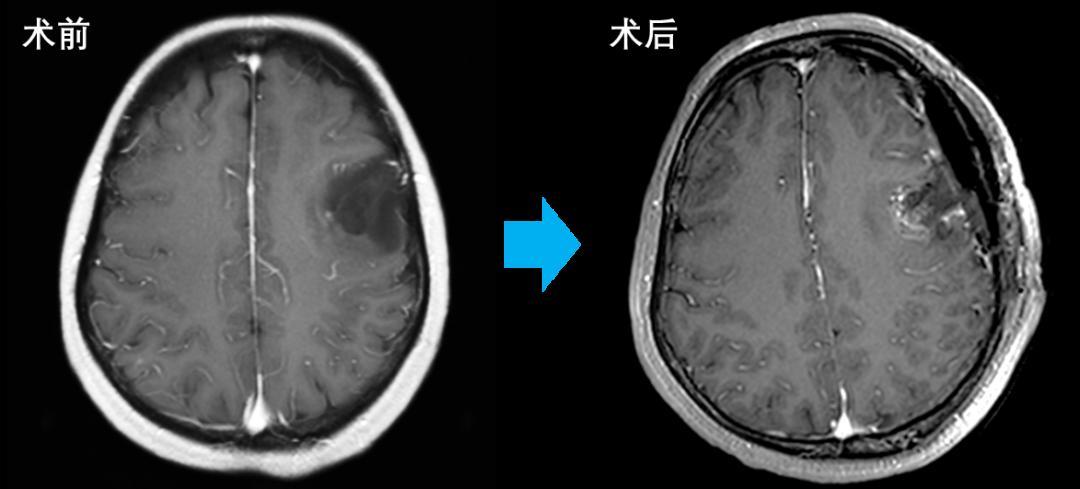

近日,国家区域医疗中心复旦大学附属华山医院福建医院、福建医科大学附属第一医院(滨海院区)(简称:华山医院福建医院)神经外科成功应用完全自主知识产权, 国际首创的全自动特定功能神经束成像技术辅助唤醒麻醉开颅, 为一例累及左额语言区的胶质瘤患者成功进行了手术。

患者为一名中年女性,因反复肢体抽搐,癫痫发作2年就医。检查时发现左侧额叶语言功能区附近有胶质瘤,如果不进行手术切除,肿瘤会逐步扩大,侵犯周围的语言功能区及口唇运动区,最终会影响运动功能区,导致运动性失语和右侧口角歪斜及肢体瘫痪。

术前,患者通过设定的工作流程完成影像扫描,技术团队辅助完成自动化语言功能神经传导束重建,并通过现有导航设备进行术中精确定位。

手术最大限度实现了切除肿瘤的同时保存患者的语言功能。